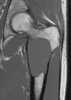

Simple unicameral bone cyst

A bone cyst or geode is a cyst that forms in bone. Types include: Unicameral bone cyst Aneurysmal bone cyst Traumatic bone cyst Diagnosis On CT scans, bone cysts that have a radiodensity of 20 Hounsfield units (HU) or less, and are osteolytic, tend to be aneurysmal bone cysts.In contrast, intraosseous lipomas have a lower radiodensity of -40 to -60 HU. Treatment and Prevention Simple (Unicameral) Bone Cyst Some unicameral bone cysts may spontaneously resolve without medical intervention. [Source: Wikipedia ]